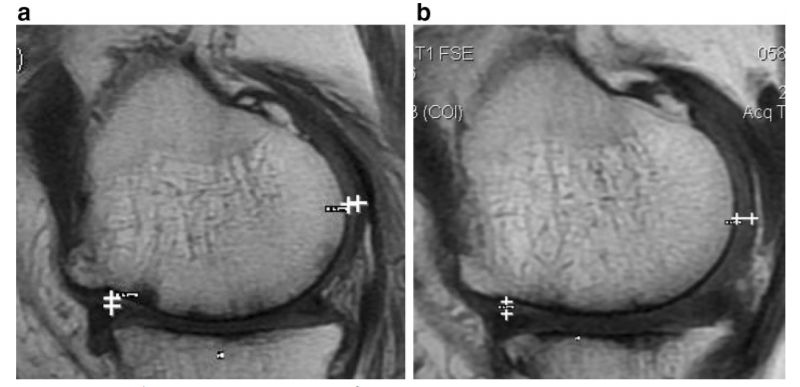

研究结果:治疗后,2年后WOMAC评分也得到改善。6分钟内步行距离也显著增加。60%的病人的软骨体积增加。

如上图所示,左图为治疗前,右图为治疗后,白色“+”处示意软骨增厚。